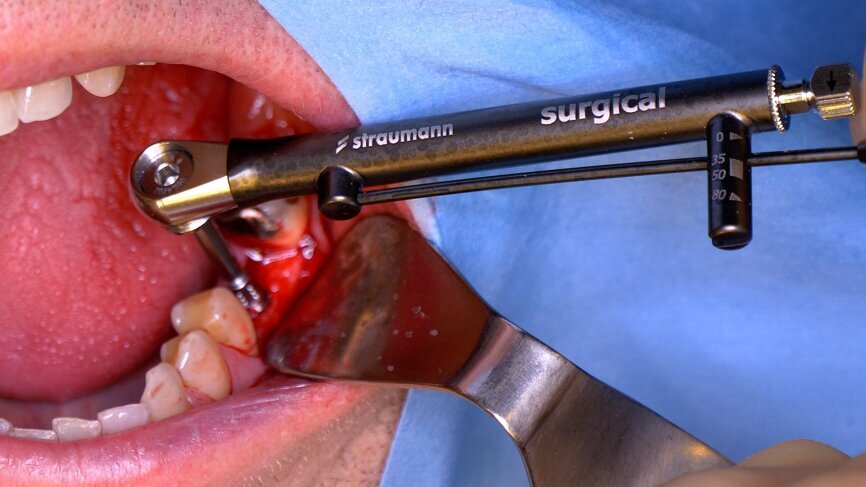

After 12 weeks, Salvesen removed the temporary crown, revealing that the soft tissue had healed very well (Fig. 15). He then began the digital workflow. For the final crown, a digital impression was taken with a 3Shape intra-oral scanner, using a Straumann CARES scan body. A monolithic zirconia crown was then seated passively on to the implant in a healed and preconditioned soft-tissue environment (Figs. 16–19).

Fig. 18: Final crown in position, lateral view.